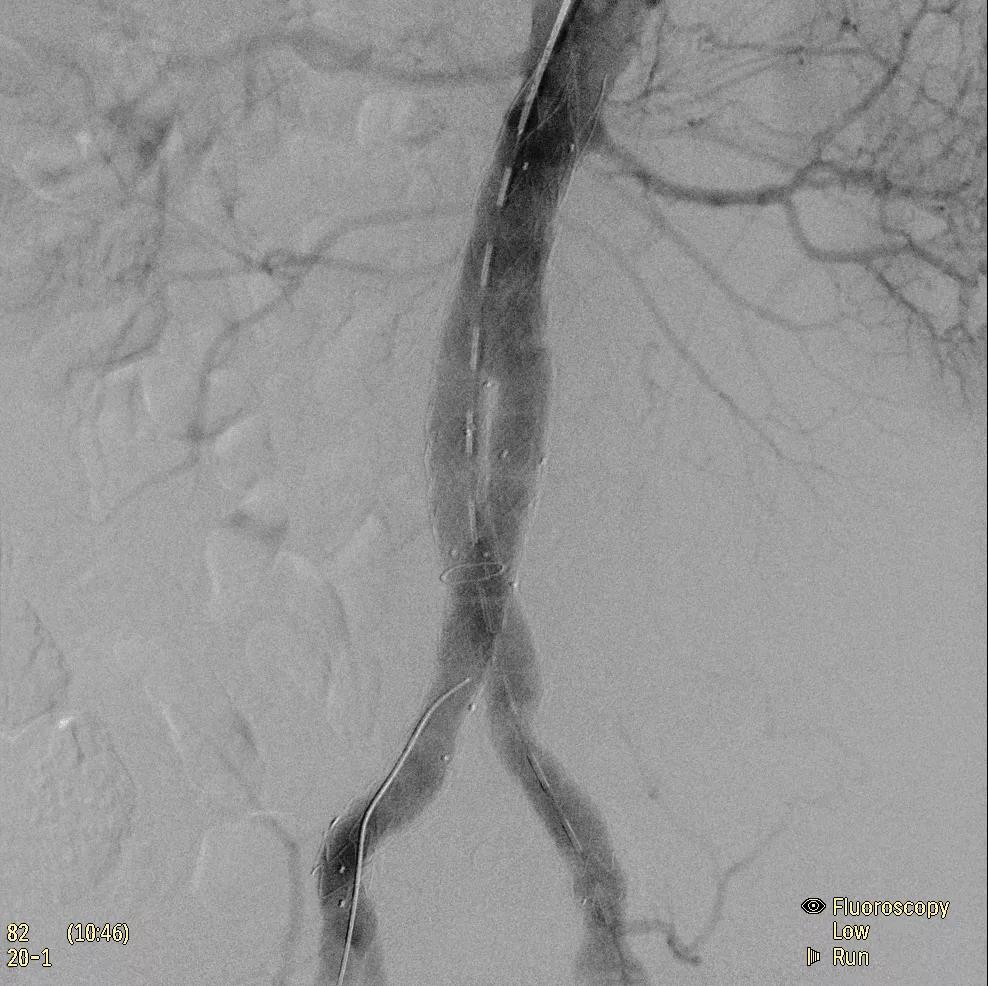

為了獲得清晰的高質(zhì)量圖像,Zenition 70 采用了與公司Azurion平臺(tái)相同的圖像處理算法,可提供患者解剖結(jié)構(gòu)的高清可視化和更大的可視區(qū)域。飛利浦的MetalSmart軟件等功能可確保圖像質(zhì)量,該軟件可自動(dòng)調(diào)整圖像的對比度和亮度,以便在視野中存在金屬物體(如植入物)時(shí)提高圖像質(zhì)量 - 這一特性使Zenition 70在整形外科中特別有用。